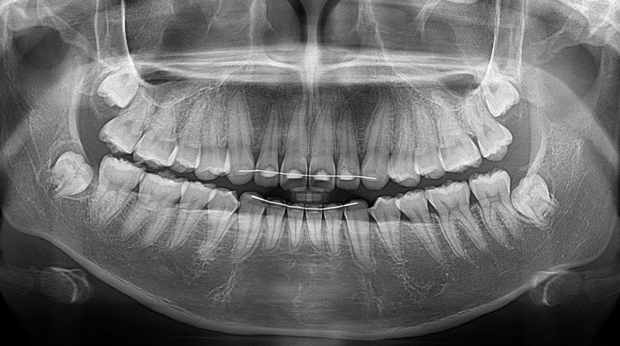

임플란트와 사랑니 발치는 외과적 시술로 잇몸을 절개하는 외과적 시술은

짧으면 짧을 수록 시술 후 붓기와 통증이 최소화됩니다.

치과의사 경력 14년차 구강외과 전문의가 빠르고 안전하게, 아프지 않게 수술해 드립니다.

치과경력 14년차 구강외과 전문의